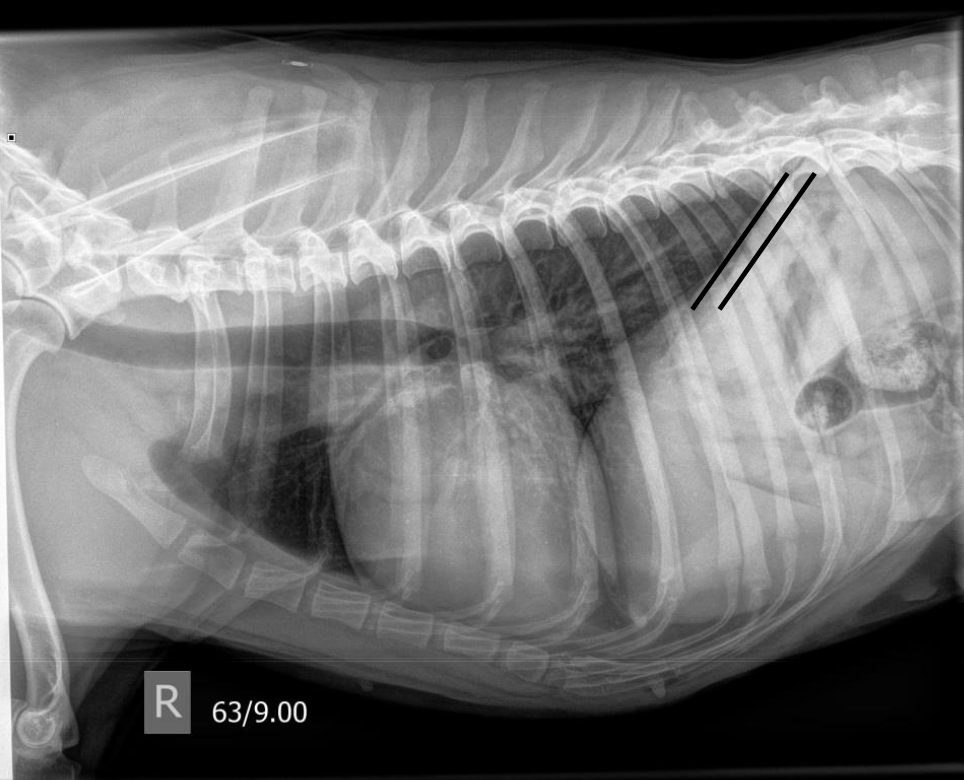

what are the lines demonstrating

crura of the diaphragm parallel in right lateral view

heart long and in contact with sternum